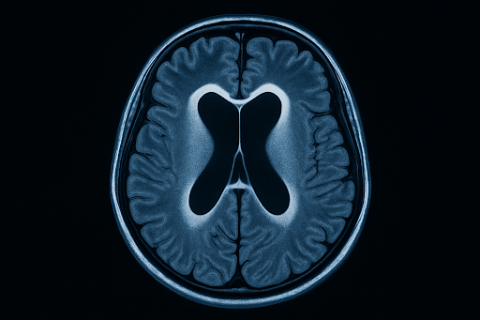

A hidrocefalia é diagnosticada principalmente por exames de imagem, que permitem visualizar com precisão a dilatação dos ventrículos cerebrais e, em muitos casos, identificar a origem do acúmulo de líquido. A escolha do exame depende da idade do paciente, da gravidade dos sintomas e da necessidade de investigação complementar.

Ressonância Magnética (RM)

A RM é considerada o padrão-ouro na avaliação da hidrocefalia, por oferecer uma análise minuciosa da anatomia cerebral e da circulação do líquido cefalorraquidiano (LCR).

Ela é especialmente útil para:

- Diferenciar hidrocefalia de atrofia cerebral.

- Investigar causas secundárias, como tumores, estenoses ou cistos.

- Avaliar a morfologia ventricular e a pressão exercida sobre estruturas adjacentes.

Exames de imagem, como tomografia e ressonância magnética, revelam a dilatação dos ventrículos cerebrais e ajudam a identificar a causa do acúmulo de líquido, como obstruções, inflamações ou alterações anatômicas.

Sim, a tomografia pode identificar ventrículos dilatados com rapidez. No entanto, a ressonância magnética oferece uma análise mais detalhada, especialmente em casos crônicos ou complexos.

A hidrocefalia é uma condição séria, mas que pode ser tratada com sucesso quando diagnosticada corretamente. Os exames de imagem — especialmente a tomografia e a ressonância magnética — são fundamentais para detectar o acúmulo de líquido no cérebro, entender sua causa e guiar a conduta clínica.